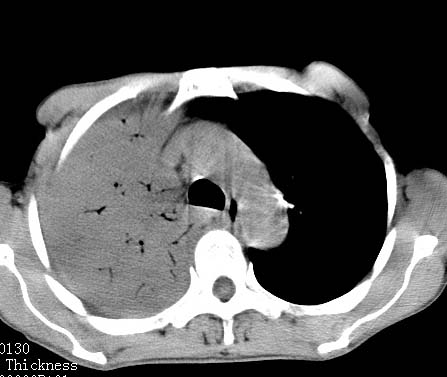

病人女 60岁 咳嗽 气促十余天,大叶性肺炎.

右肺上下叶均见 大片状密度增高影,边界清晰,其内可见支气管充气征,气管支气管通畅。纵膈略向右移位,其内无肿大淋巴结影。首先考虑炎性病变。不排除一些特异性的炎症。不知道发烧吗??wbc高吗??建议治疗后复查!!